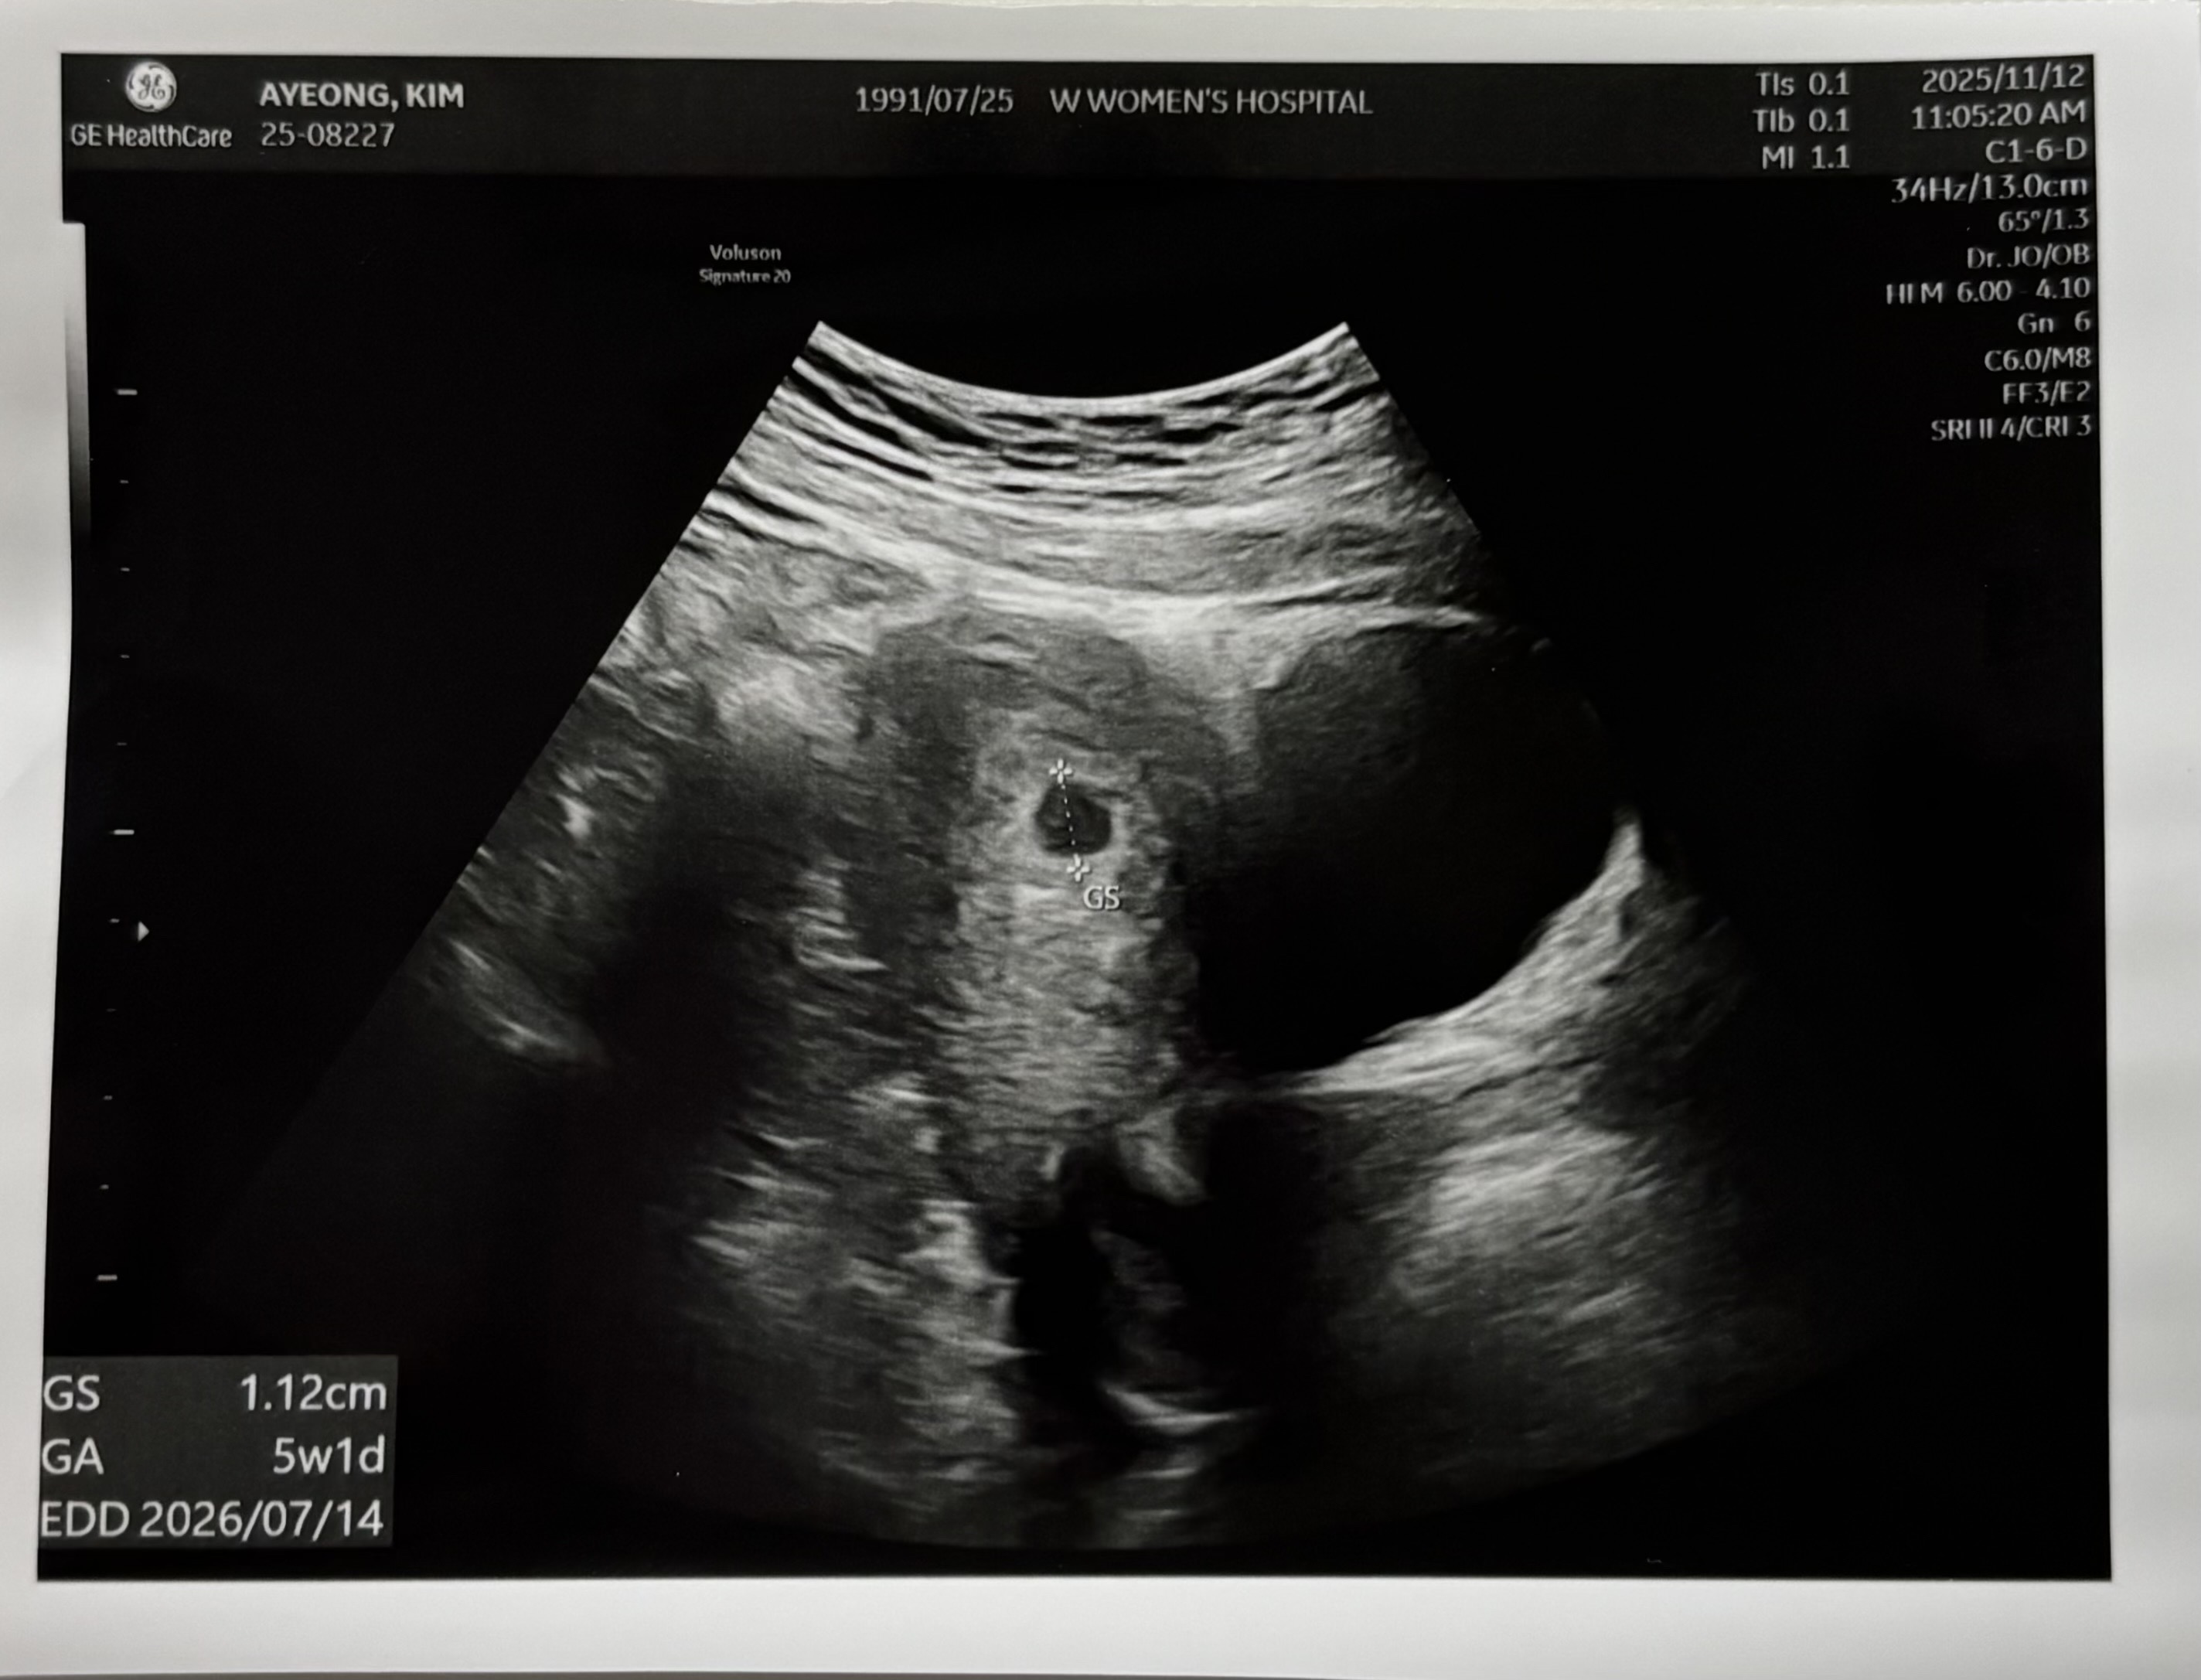

막생10월4일 11월12일에 두번째 아기집 보고 왔어요! 4주차때는 너무 작은 콩알이었는데 한주 지났다고 이렇게 컸더라구요 ㅎㅎ 아직 난황은 안보이는거 같은데 괜찮은가요? ㅠㅠ 이제 2주뒤에 오라고해서 11월26일에 가거든요 ㅠㅠ 불안해 하지 않아도 괜찮겠죠?

배란이 늦은거 같다고 하시는데 ㅠㅠㅠ 모르겠어요 출산일이 처음에 7.11에서 지금은 7.14일로 바꼈어요